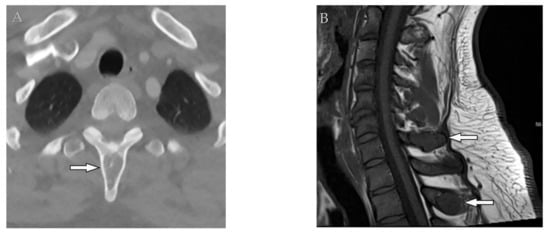

Tuberculosis spondylodiskitis has a more gradual and chronic clinical course, which leads to multi-level involvement and paravertebral cold abscess formation with well-circumscribed thin wall. Subligamentous spread of infection to adjacent vertebral levels, relative preservation of intervertebral disk, and kyphotic angulation (gibbous deformity) are other imaging findings. CT scan is more sensitive in delineating calcification within paravertebral cold abscess, end plate erosion, and bony fragment visualization (Figure 13) [39,42].

Figure 13.

A 65-year-old man with fever, weight loss, and night sweeting. The non-contrast-enhanced CT (bone window) in axial plane (a) shows paraspinal soft tissue mass with erosion of right lateral aspect of adjacent vertebral body. Sagittal T2W image of another patient with the same pathology (b) shows hypersignal intensity within T8-T9 vertebral bodies with also intervertebral disc destruction and narrowing of spinal canal pushing the spinal cord posteriorly. Axial T1WFS + C (c) identified the enhancing paraspinal mass with peripheral rim enhancement (arrow) in its left posteromedial side, which is suggestive of abscess formation. Culture of aspirated pus under guide of CT was compatible with tuberculosis infection.